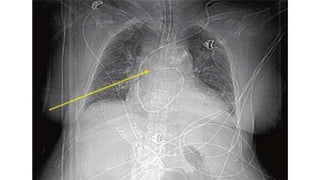

CHEST X RAY (CXR) Check for..

A – airways

B – basal lungs & pleura

C – cardio mediastinum

D – disabilities (visible fractures etc)

E – everything else

• R > L diaphragm gap (not more than 3cm)

• Cardiothoracic ratio not more than <55%

• Trachea diameter < 25mm in males/ < 21mm in females.

• Aortic notch should be visible.

• Any gastric abnormalities (bubbles)

CHEST X RAY(CXR) Check for.. A – airways B – basal lungs & pleura C – cardio mediastinum D – disabilities (visible fractures etc) E – everything else • R > L diaphragm gap (not more than 3cm) • Cardiothoracic ratio not more than <55% • Trachea diameter < 25mm in males/ < 21mm in females. • Aortic notch should be visible. • Any gastric abnormalities (bubbles)